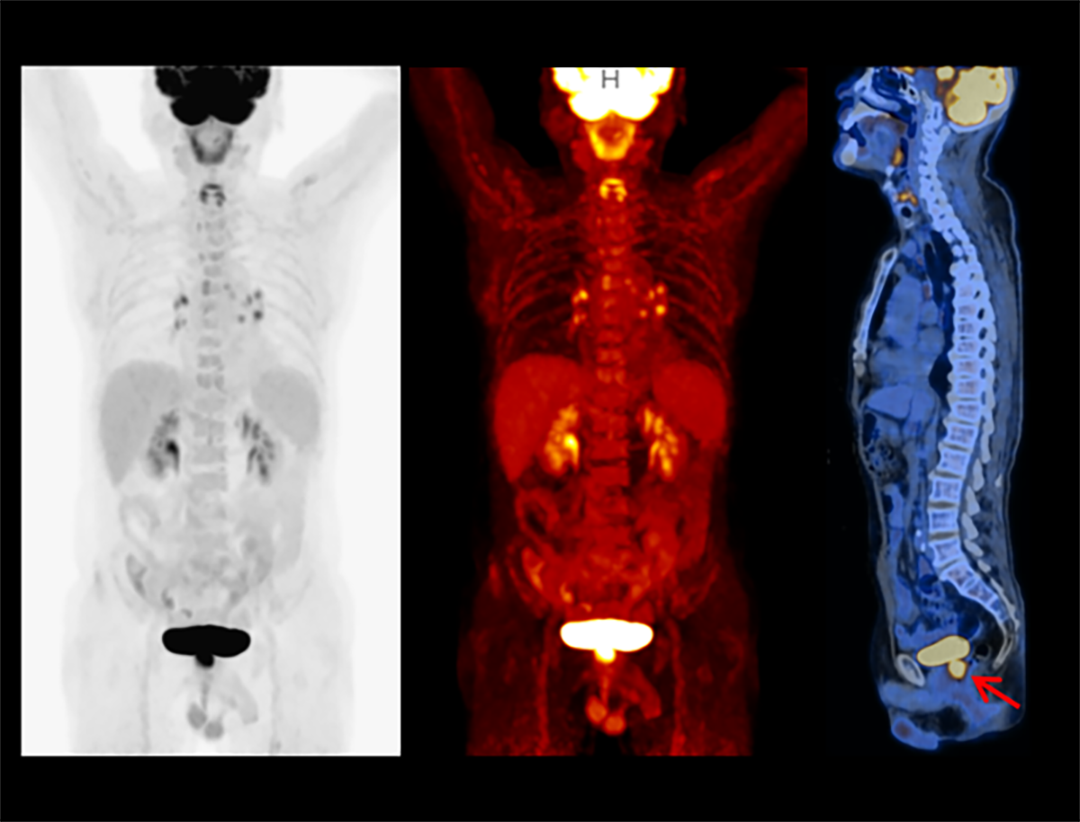

Integrated Oncology Application

The uMI 550 offers a comprehensive solution package for tumor diagnosis and post-therapeutic evaluation on the operation console.